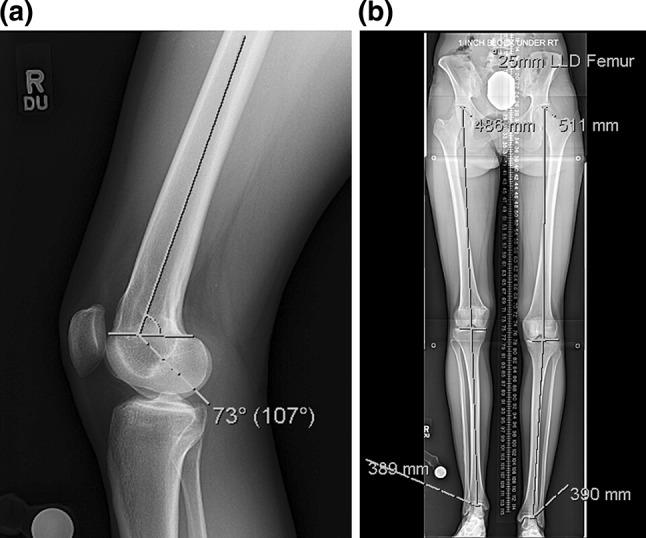

Salter Harris fractures of the distal femur can lead to growth disturbance with resulting leg length inequality and knee deformity. We have looked at a case series (3) of patients who presented with a distal femur flexion malunion and shortening treated with a distal femoral osteotomy and plating and a proximal femoral osteotomy with a magnetic internal lengthening nail. Does a two-level osteotomy and internal fixation approach provide a reliable result both radiographically and functionally? The average knee extension loss was 12°, LLD 47 mm, PDFA 65°, MAD 2 mm. The patients were treated with an acute, posterior, opening wedge osteotomy of the distal femur stabilized with a lateral plate and screws and grafted with cancellous chips and putty. A second osteotomy was made proximally in the femur percutaneously, and the internal lengthening nail was inserted. Lengthening was done at approximately 1 mm/day. The average extension gain was 12°; amount of lengthening at the proximal site was 40 mm, LLD was 3 mm. The average PDFA was 81°, and MAD 3 mm. There were no complications. Functional results were excellent. Bone healing index was 24 days/cm. The average distance from the distal osteotomy to the joint line was 57 mm. The technique of two-level femur osteotomy stabilized with a plate and lengthening nail yielded excellent results with acceptable correction of deformity, full knee extension, and improved function. There were no complications including implant failure, infection, need for blood transfusion, knee stiffness, nonunion, compartment syndrome, or malunion.

摘要